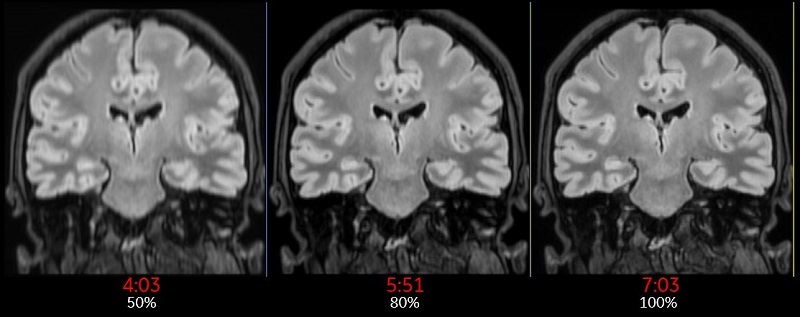

Slice Resolution %

The Slice Resolution % value is used to define the zero-padding on both sides of the kz direction in k-space. For example, when Slice Resolution (%) is set to 50, it is equivalent to the old ZIP x 2 Imaging Option. When Slice Resolution (%) is set to 25, it is equivalent to old ZIP x4 Imaging Option.

Use Slice Resolution % to reduce the number of slice encoding for 3D acquisitions to decrease the scan time. The tradeoff is reduced image resolution.

Slice Resolution% is annotated next to the Slice thickness annotation in the lower left corner of the image.